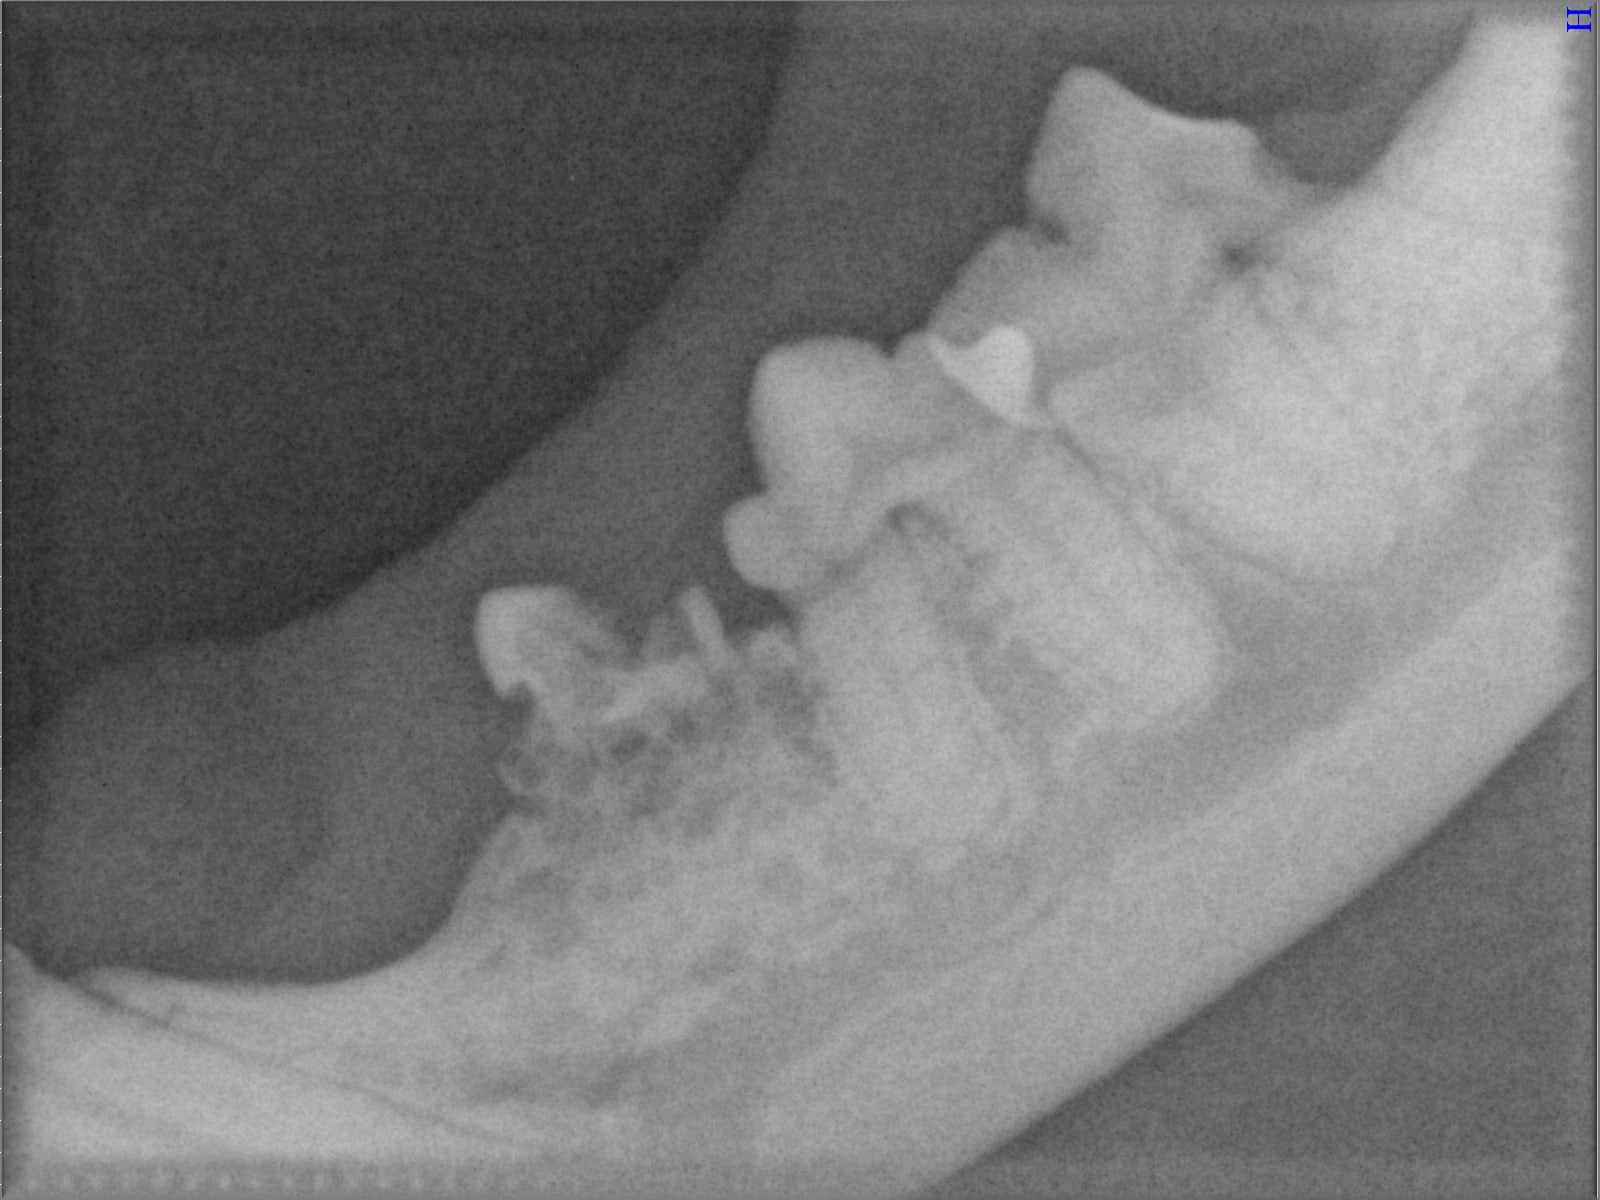

Ein entscheidender Baustein der FORL-Diagnostik ist das dentale Röntgen. Viele Läsionen sind von außen nicht sichtbar und lassen sich ausschließlich mithilfe moderner Röntgentechnik erkennen. In der Hamburger Praxis kommt digitales Dentalröntgen zum Einsatz, das detailreiche Aufnahmen bei geringer Strahlenbelastung ermöglicht. So kann FORL bereits in frühen Stadien diagnostiziert werden.

Das sehen Sie von außen – so sieht es auf den Röntgenbildern aus.

FORL Katze Röntgenbild

Röntgenbilder